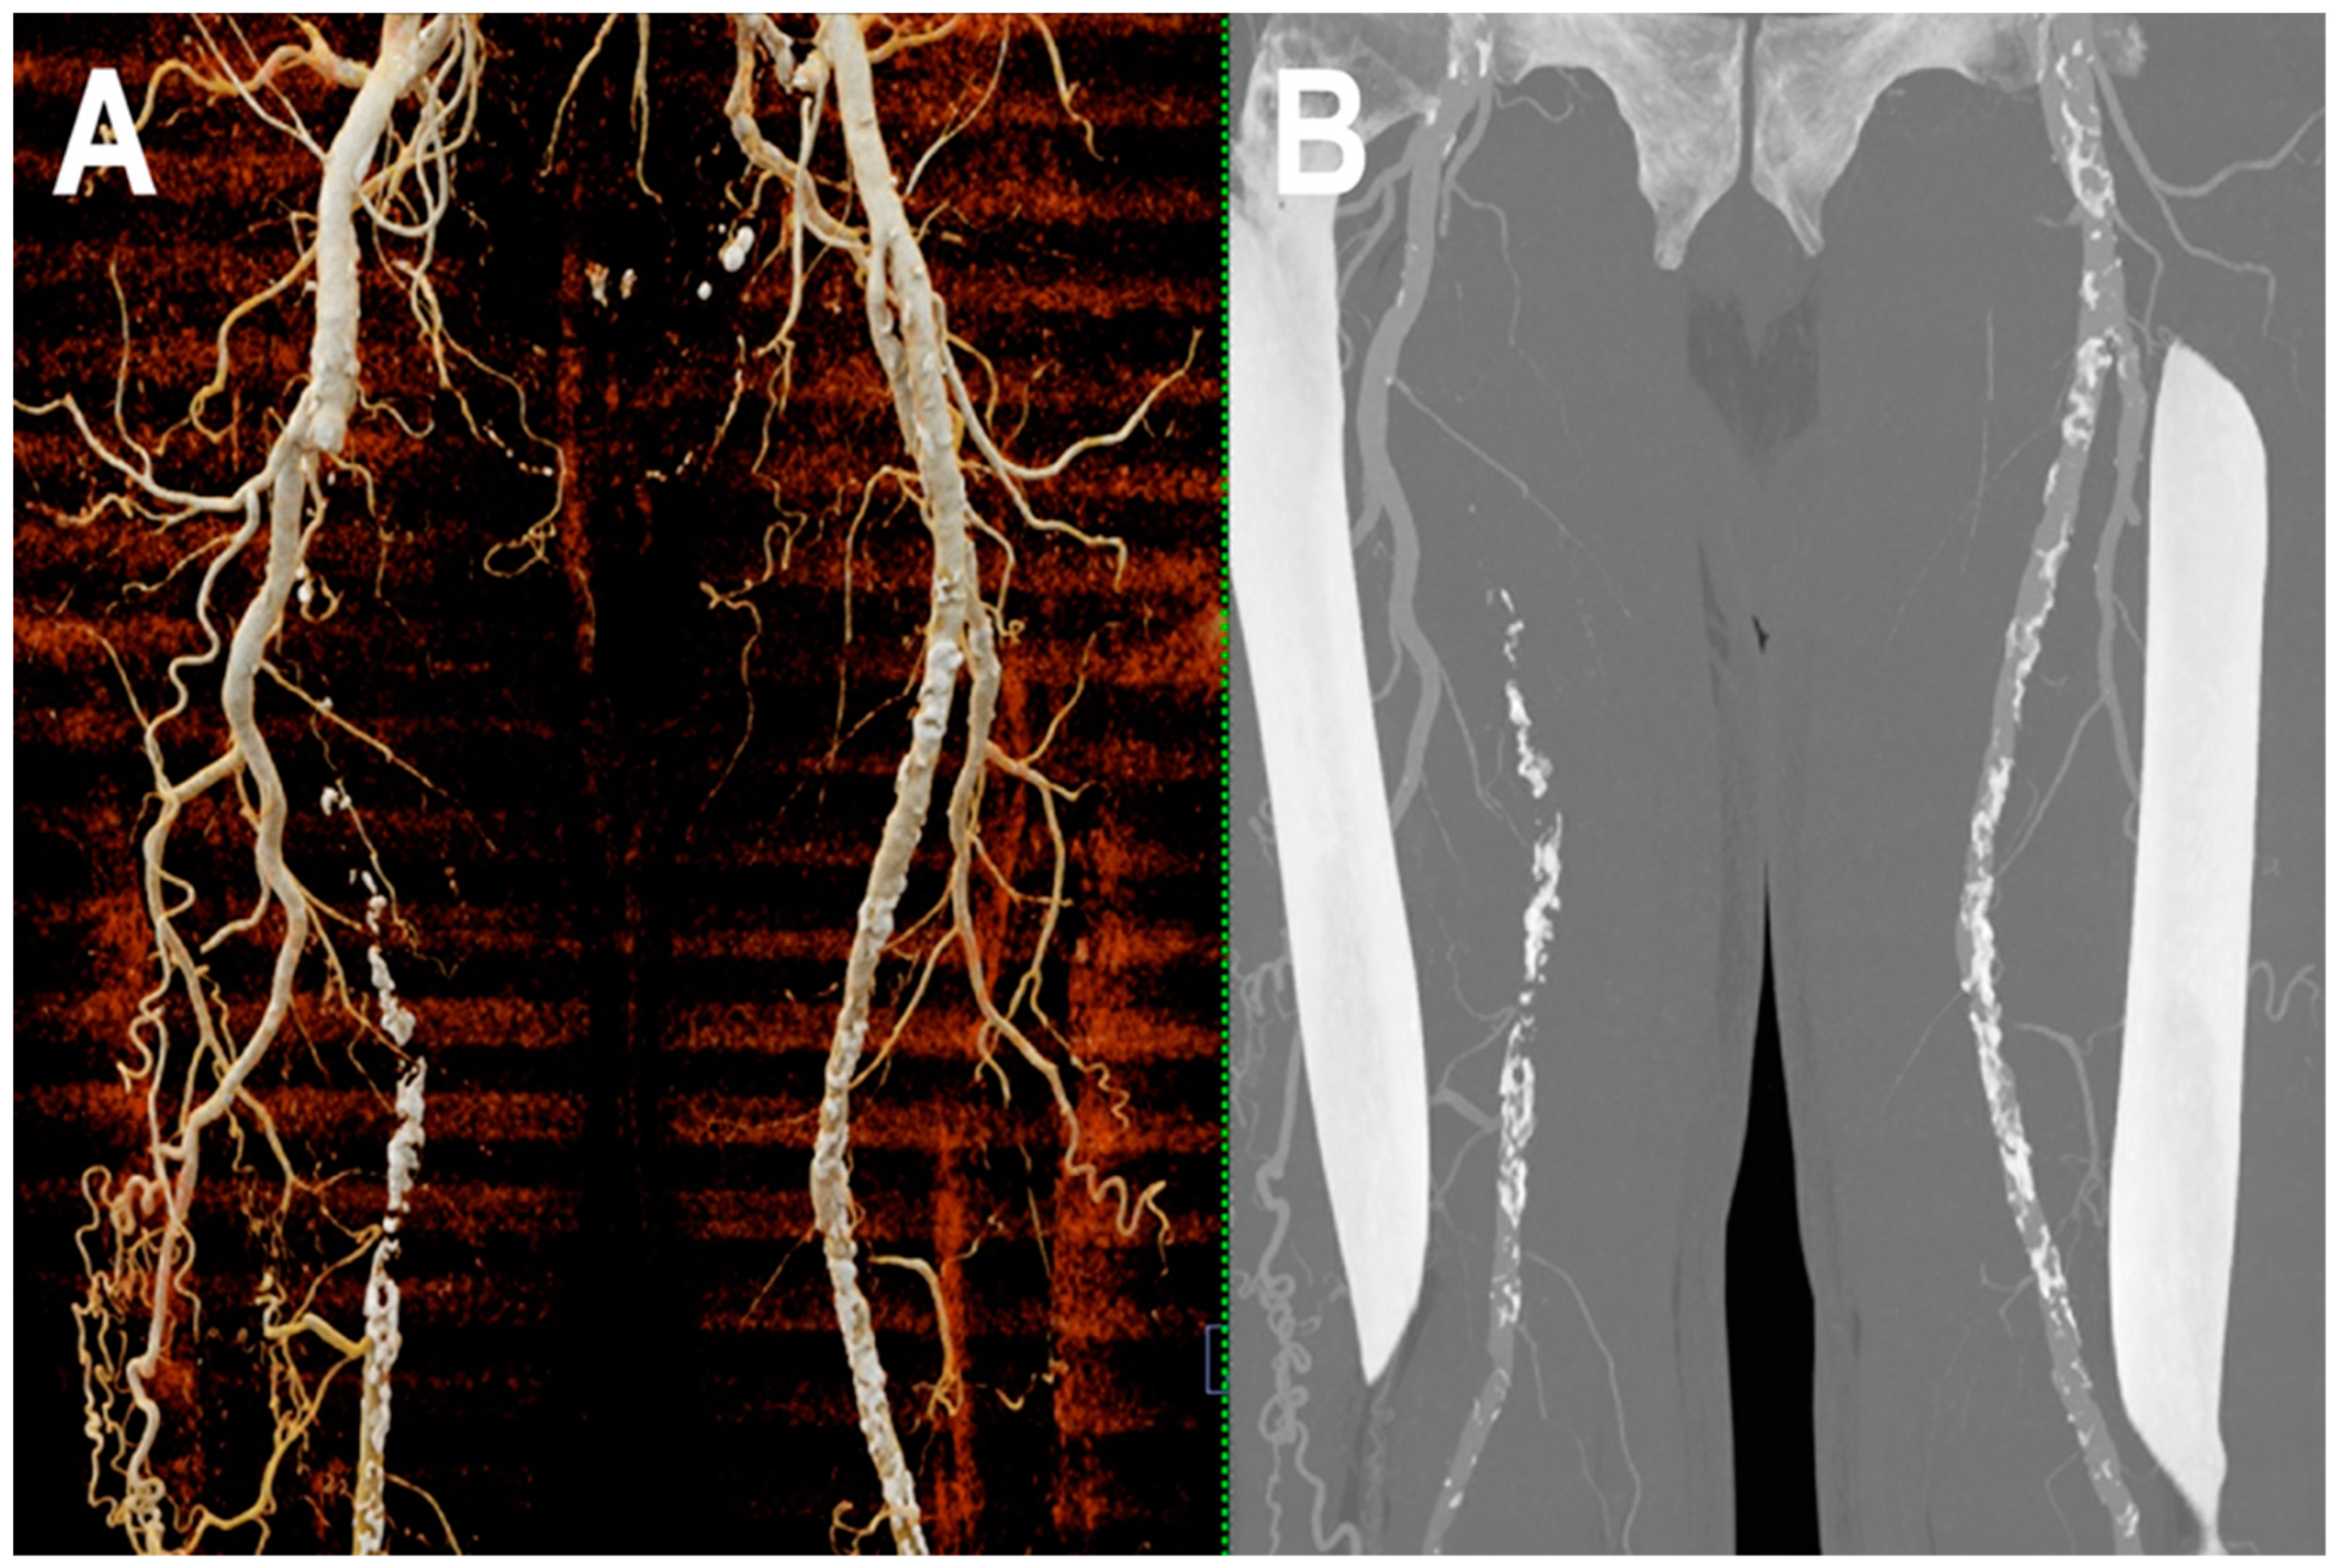

- Shwaiki, O.; Rashwan, B.; Fink, M.A.; Kirksey, L.; Gadani, S.; Karuppasamy, K.; Melzig, C.; Thompson, D.; D’Amico, G.; Rengier, F.; et al. Lower extremity CT angiography in peripheral arterial disease: From the established approach to evolving technical developments. Int. J. Cardiovasc. Imaging 2021, 37, 3101–3114. [Google Scholar] [CrossRef] [PubMed]

- Tanaka, R.; Yoshioka, K.; Takagi, H.; Schuijf, J.D.; Arakita, K. Novel developments in non-invasive imaging of peripheral arterial disease with CT: Experience with state-of-the-art, ultra-high-resolution CT and subtraction imaging. Clin. Radiol. 2019, 74, 51–58. [Google Scholar] [CrossRef]

- Leng, S.; Yu, Z.; Halaweish, A.; Kappler, S.; Hahn, K.; Henning, A.; Li, Z.; Lane, J.; Levin, D.L.; Jorgensen, S.; et al. Dose-efficient ultrahigh-resolution scan mode using a photon counting detector computed tomography system. J. Med. Imaging 2016, 3, 043504. [Google Scholar] [CrossRef]